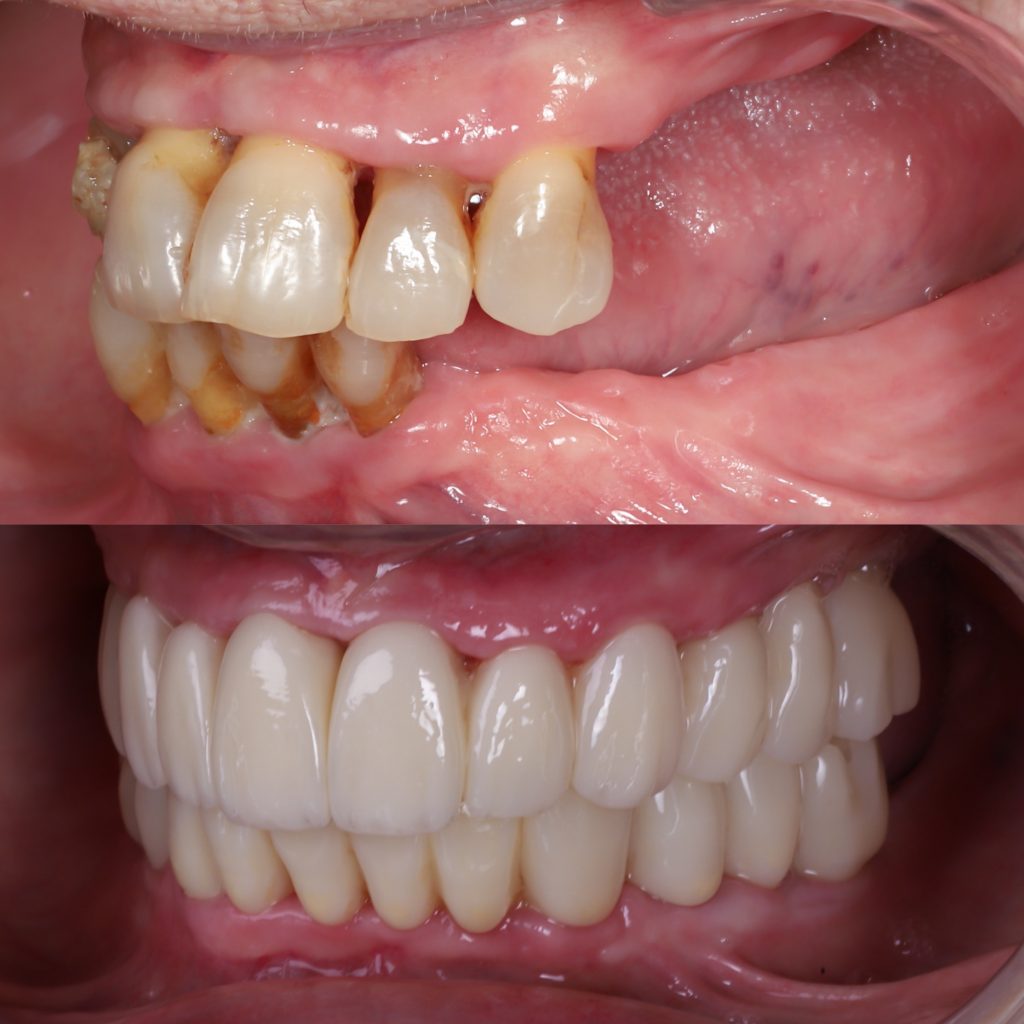

Historias de transformación

Si alguna vez te han dicho que tu caso no tiene solución, en Alejandro Prieto Dental desafiamos los límites de la odontología para ofrecerte la respuesta que estabas buscando.

Before

After

Visualizar la transformación

Los cambios de imagen de la sonrisa favorecen mejoras cuidadosas y matizadas, para obtener resultados naturales que garanticen el equilibrio general y la armonía facial.